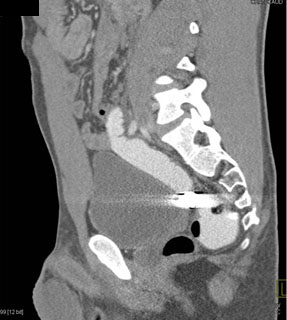

In this patient with a gunshot to the pelvis contrast was placed in rectum and demonstrated

rectal perforation